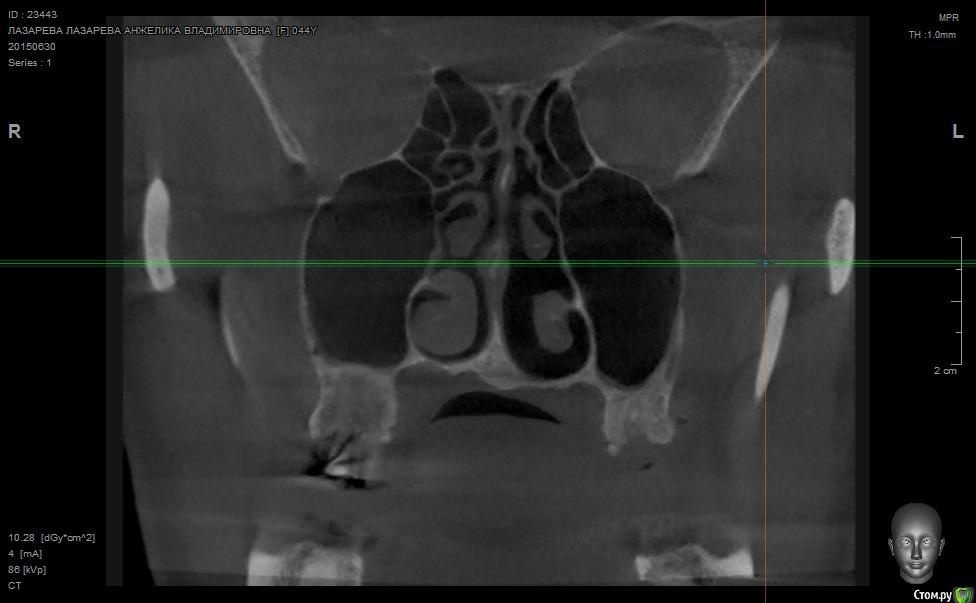

Angelika Опубликовано 2 июля, 2015 Поделиться Опубликовано 2 июля, 2015 Добрый день!Помогите,пожалуйста!!!!!!8 мая имплантолог(!) удалил 2 зуба-27(резерцин-формалиновый) и 28 (нелеченный).Удаление было очень долгим и травматичным,почуяв неладное,хотела убежать прямо из кресла.Последствия-одонтогенный гайморит,не считая незаживающих лунок .В начале июня отлежела в ЧЛХ(антибиотики,физио).26 июня сделала КТ.Нос пришел в норму более-менее,а вот челюсть....((((( Из заключения: 26,27,зубы отсутствуют. В альвеолярном отростке верхней челюсти в области отсутствующего 26 и 27 зуба визуализируется дефект костной ткани размерами до 9,6*14,0*7,2 мм с неровными и нечеткими контурами, с множественными мелкими и крупными секвестрами, с разрушеннымиоральной кортикальной пластинкой альвеолярного отростка верхней челюсти на протяжении до 12,9мм, и вестибулярной замыкательной пластинкой на протяжении до 19,1 мм. Рентгенологическихпризнаков свидетельствующих о наличии свищевого хода, ороантрального соустья - не выявлено,целостность нижней стенки левой верхнечелюстной пазухи полностью восстановлена на всем протяжении. Положительная динамика от 26.05.15г. В альвеолярном отростке, в области корней отсутствующего 28 зуба, определяются нечеткиеконтуры лунки удаленного зуба и единичный фрагмент корня размерами до 1,9*1,7*2,7 мм. В областиотсутствующего 28 зуба и бугра верхней челюсти слева визуализируются единичные мелкие участки остеопороза костной ткани альвеолярного отростка верхней челюсти, в следствие исхода воспалительного процесса. Посоветуйте,пожалуйста,нужно ли удалять обломок корня 28 зуба,если он такой маленький,а лунка уже затянулась.Что мне делать,как это залечить,болит вся челюсть с левой стороны.(((((( О имплантах и забыла уже,восстановиться бы после такой травмы.....Помогите!!! Что делать,как залечить все это?Снимки прилагаю. Ссылка на комментарий

Alejandro Опубликовано 2 июля, 2015 Поделиться Опубликовано 2 июля, 2015 На бумаге страшнее, чем на снимке. Лучший врач для Вас теперь - время. Со временем, кстати, станет понятно: что делать с остатком корня, экстренности пока никакой нет. Успокойтесь, сложные удаления довольно часто встречаются. Очень хорошо, что нет ороантрального сообщения. 2 Ссылка на комментарий

Bier Опубликовано 5 июля, 2015 Поделиться Опубликовано 5 июля, 2015 нет. У Вас на рентгене картина свежего удаления. Т.е. в рамках нормы 2 Ссылка на комментарий

Bier Опубликовано 7 июля, 2015 Поделиться Опубликовано 7 июля, 2015 думаю, что проблем там нет. На снимке все не так плохо, как в описании. Все хорошо будет. Ссылка на комментарий